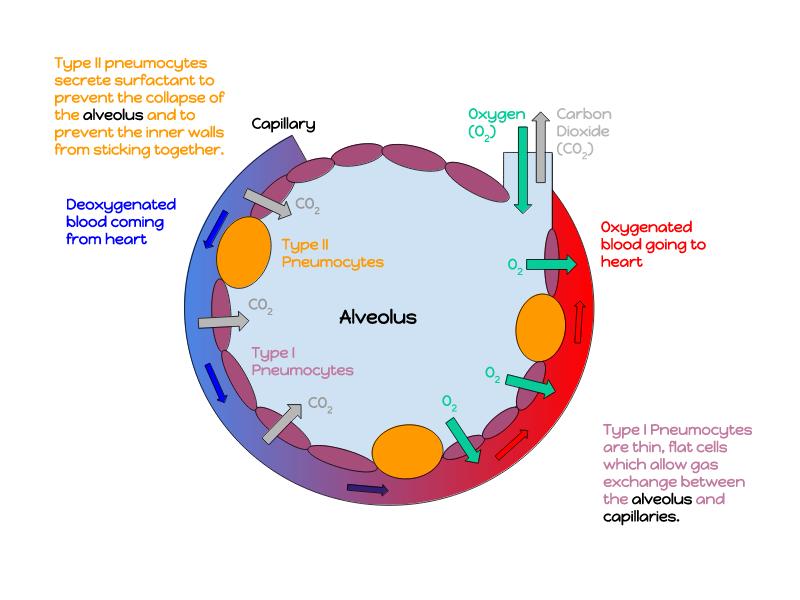

The cardiovascular system needs to be connected to the respiratory system.Path of O2 and CO2

- List complete

- With layers

- And cells

- And function of each

Components of the Blood-Air Barrier?

What other barrier systems are found in the body?

What are the purpose of each of these barrier systems? Connected with physiology will unlock the pathology.

Barriers